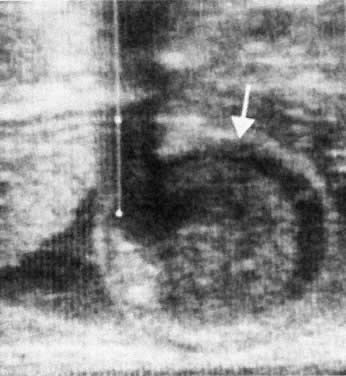

Ultrasound imaging techniques, introduced in the late 1970s, constitute a major advance in the management of maternal blood group alloimmunization.43 Ultrasound allows an estimation of placental and hepatic size and the presence or absence of edema, ascites, and other effusions (i.e., the presence or absence of hydrops fetalis; Fig. 11 and Fig. 12). Ultrasound is of great help in assessing fetal well-being (measuring the fetal biophysical profile), has increased the accuracy of placental localization, and has sharply reduced the incidence of placental trauma at amniocentesis.

Fig. 12. Sonogram of fetus with hydrops fetalis. Fetal abdomen encloses a large volume of ascitic fluid ( under white arrow) and a large liver.